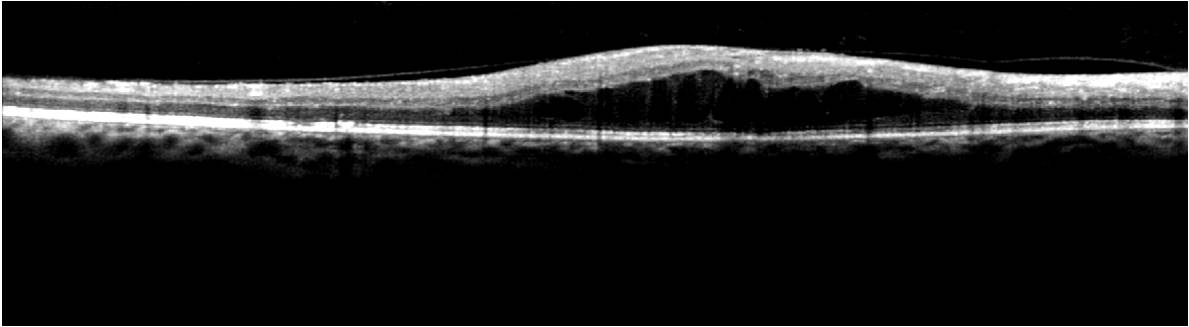

Since the error in Surface 2 is significantly high for abnormal OCT images using the proposed segmentation algorithm, the sub-retinal layer thicknesses on such abnormal images will be analyzed for the NFL and IPL layers combined (NFL++IPL, between Surface 1 and Surface 3), the INL, ONL and Outer layer (between Surface 5 and Surface 7). It is noteworthy, that although the performance of automated surface segmentation deteriorates on images with pathology, the proposed denoising and segmentation method has more reliable and repeatable performance for inner sub-retinal surface segmentation when compared to the OCTSEG system as shown in Fig. 7. The proposed method is capable of reliable estimation of the INL and ONL in image with cysts and sub-retinal disorganizations.

Figure 7: Comparative assessment of sub-retinal surface segmentation using the proposed method and the OCTSEG system on images with DME. Left column represents the automated segmentation produced by OCTSEG. Right column represents automated segmentation produced by the proposed method.